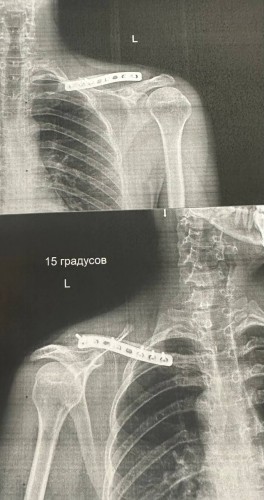

В ноябре собираюсь идти в военкомат проходить комиссию, перелом произошел в феврале 25 года, прошлую комиссию проходил в апреле, так как прошло малое количество времени после остеосинтеза дали отсрочку на пол года.

В сентябре увидел изменение в расписании болезней, убрали пункт "неудаленная метал.конструкция в ключице" которая подошла бы под категорию В и оставили "осложненные переломы длинных костей с незначительным нарушением функции конечности"

До конца не понимаю, я могу двигать рукой, сами по себе движения могу делать, но при физических нагрузках на руку появляется жжение и небольшая боль в районе ключице. Подпадает ли это под пункт В и дальнейшее получения военника и как врачи проверяют жалобы на подобные неудобства ?

photo.jpg